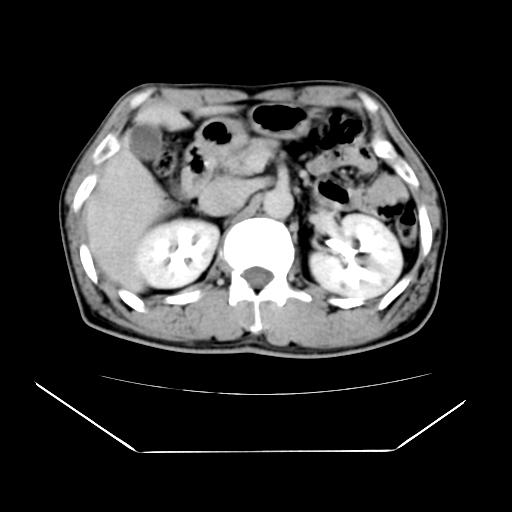

男性,55岁,外院体检afp明显升高,但b超未发现异常,否认乙肝病史。来我院ct增强。有延时扫描。

延时扫描完全充填,血管瘤

肝脏右叶动脉期可见低密度影,至延迟期被充填,考虑血管瘤可能性大。

肝右叶病灶

不排除肝右叶肝癌可能。

肝6段血管瘤

血管瘤可能性大。